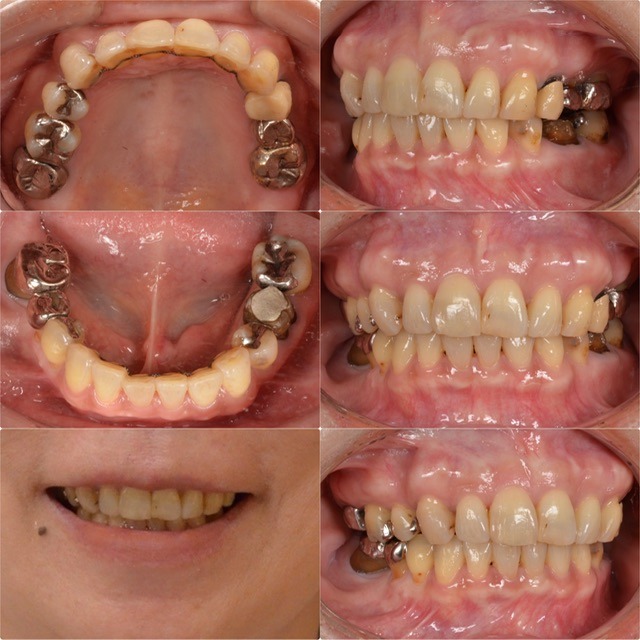

前歯部の歯並びが気になる 60代女性 2026.2.6

主訴・術前 前歯部の歯並びが気になる 術後の患者様の感想 マウスピース矯正やセラミック矯正を行って自分の納得のいく歯並びになることができたので良かったです。 マウスピースに関しては、続けられるか不安でしたが続けることができ、…